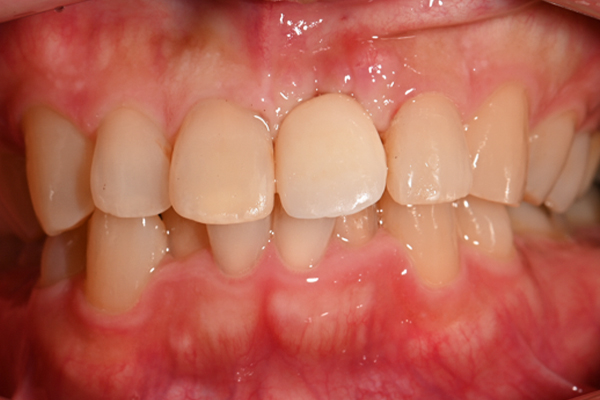

| 主訴 | 前歯が揺れる |

|---|---|

| 治療内容 | 上の前歯のインプラント治療 |

| 治療期間 | 4ヶ月 |

| 治療費 | 39万7千円 |

| 治療 リスク | インプラントの土台を入れた後最終的な歯が装着されるまで仮歯をしていただきます |